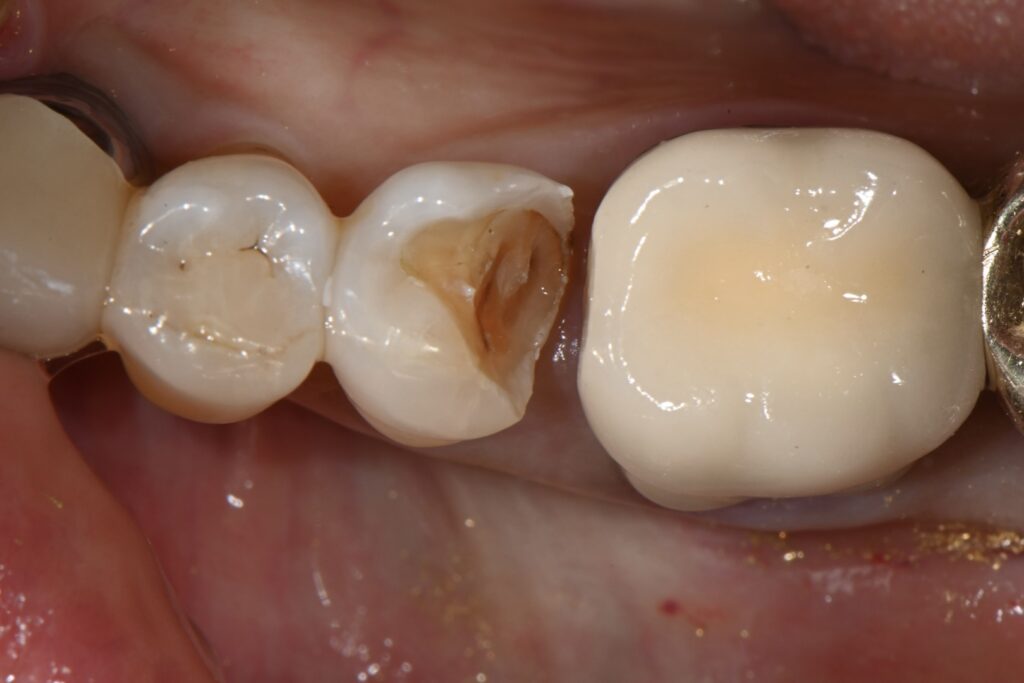

이미 깊은 충치를 확인할 수 있습니다

이정도면 꽤 깊은 부위인데요

거의 신경과 인접한 그런 부분입니다

제거해 나가는 과정입니다

여기서 더 제거를 하면 신경이 노출 될 수 있는 그런부위까지 왔습니다